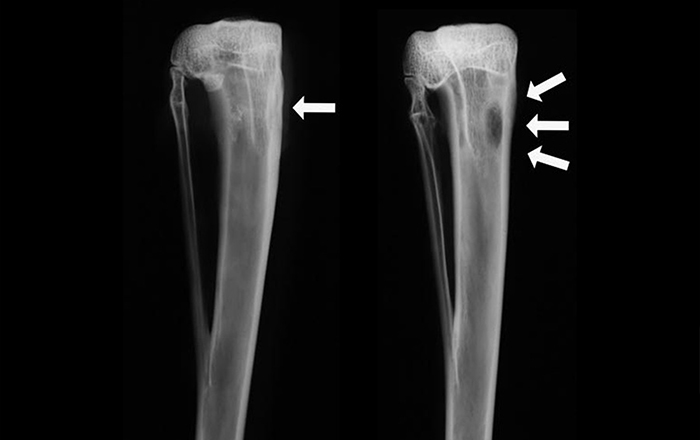

Tanı için laboratuvar testleri, görüntüleme yöntemleri (radyografi, MR, BT) ve gerektiğinde mikrobiyolojik incelemeler yapılır.